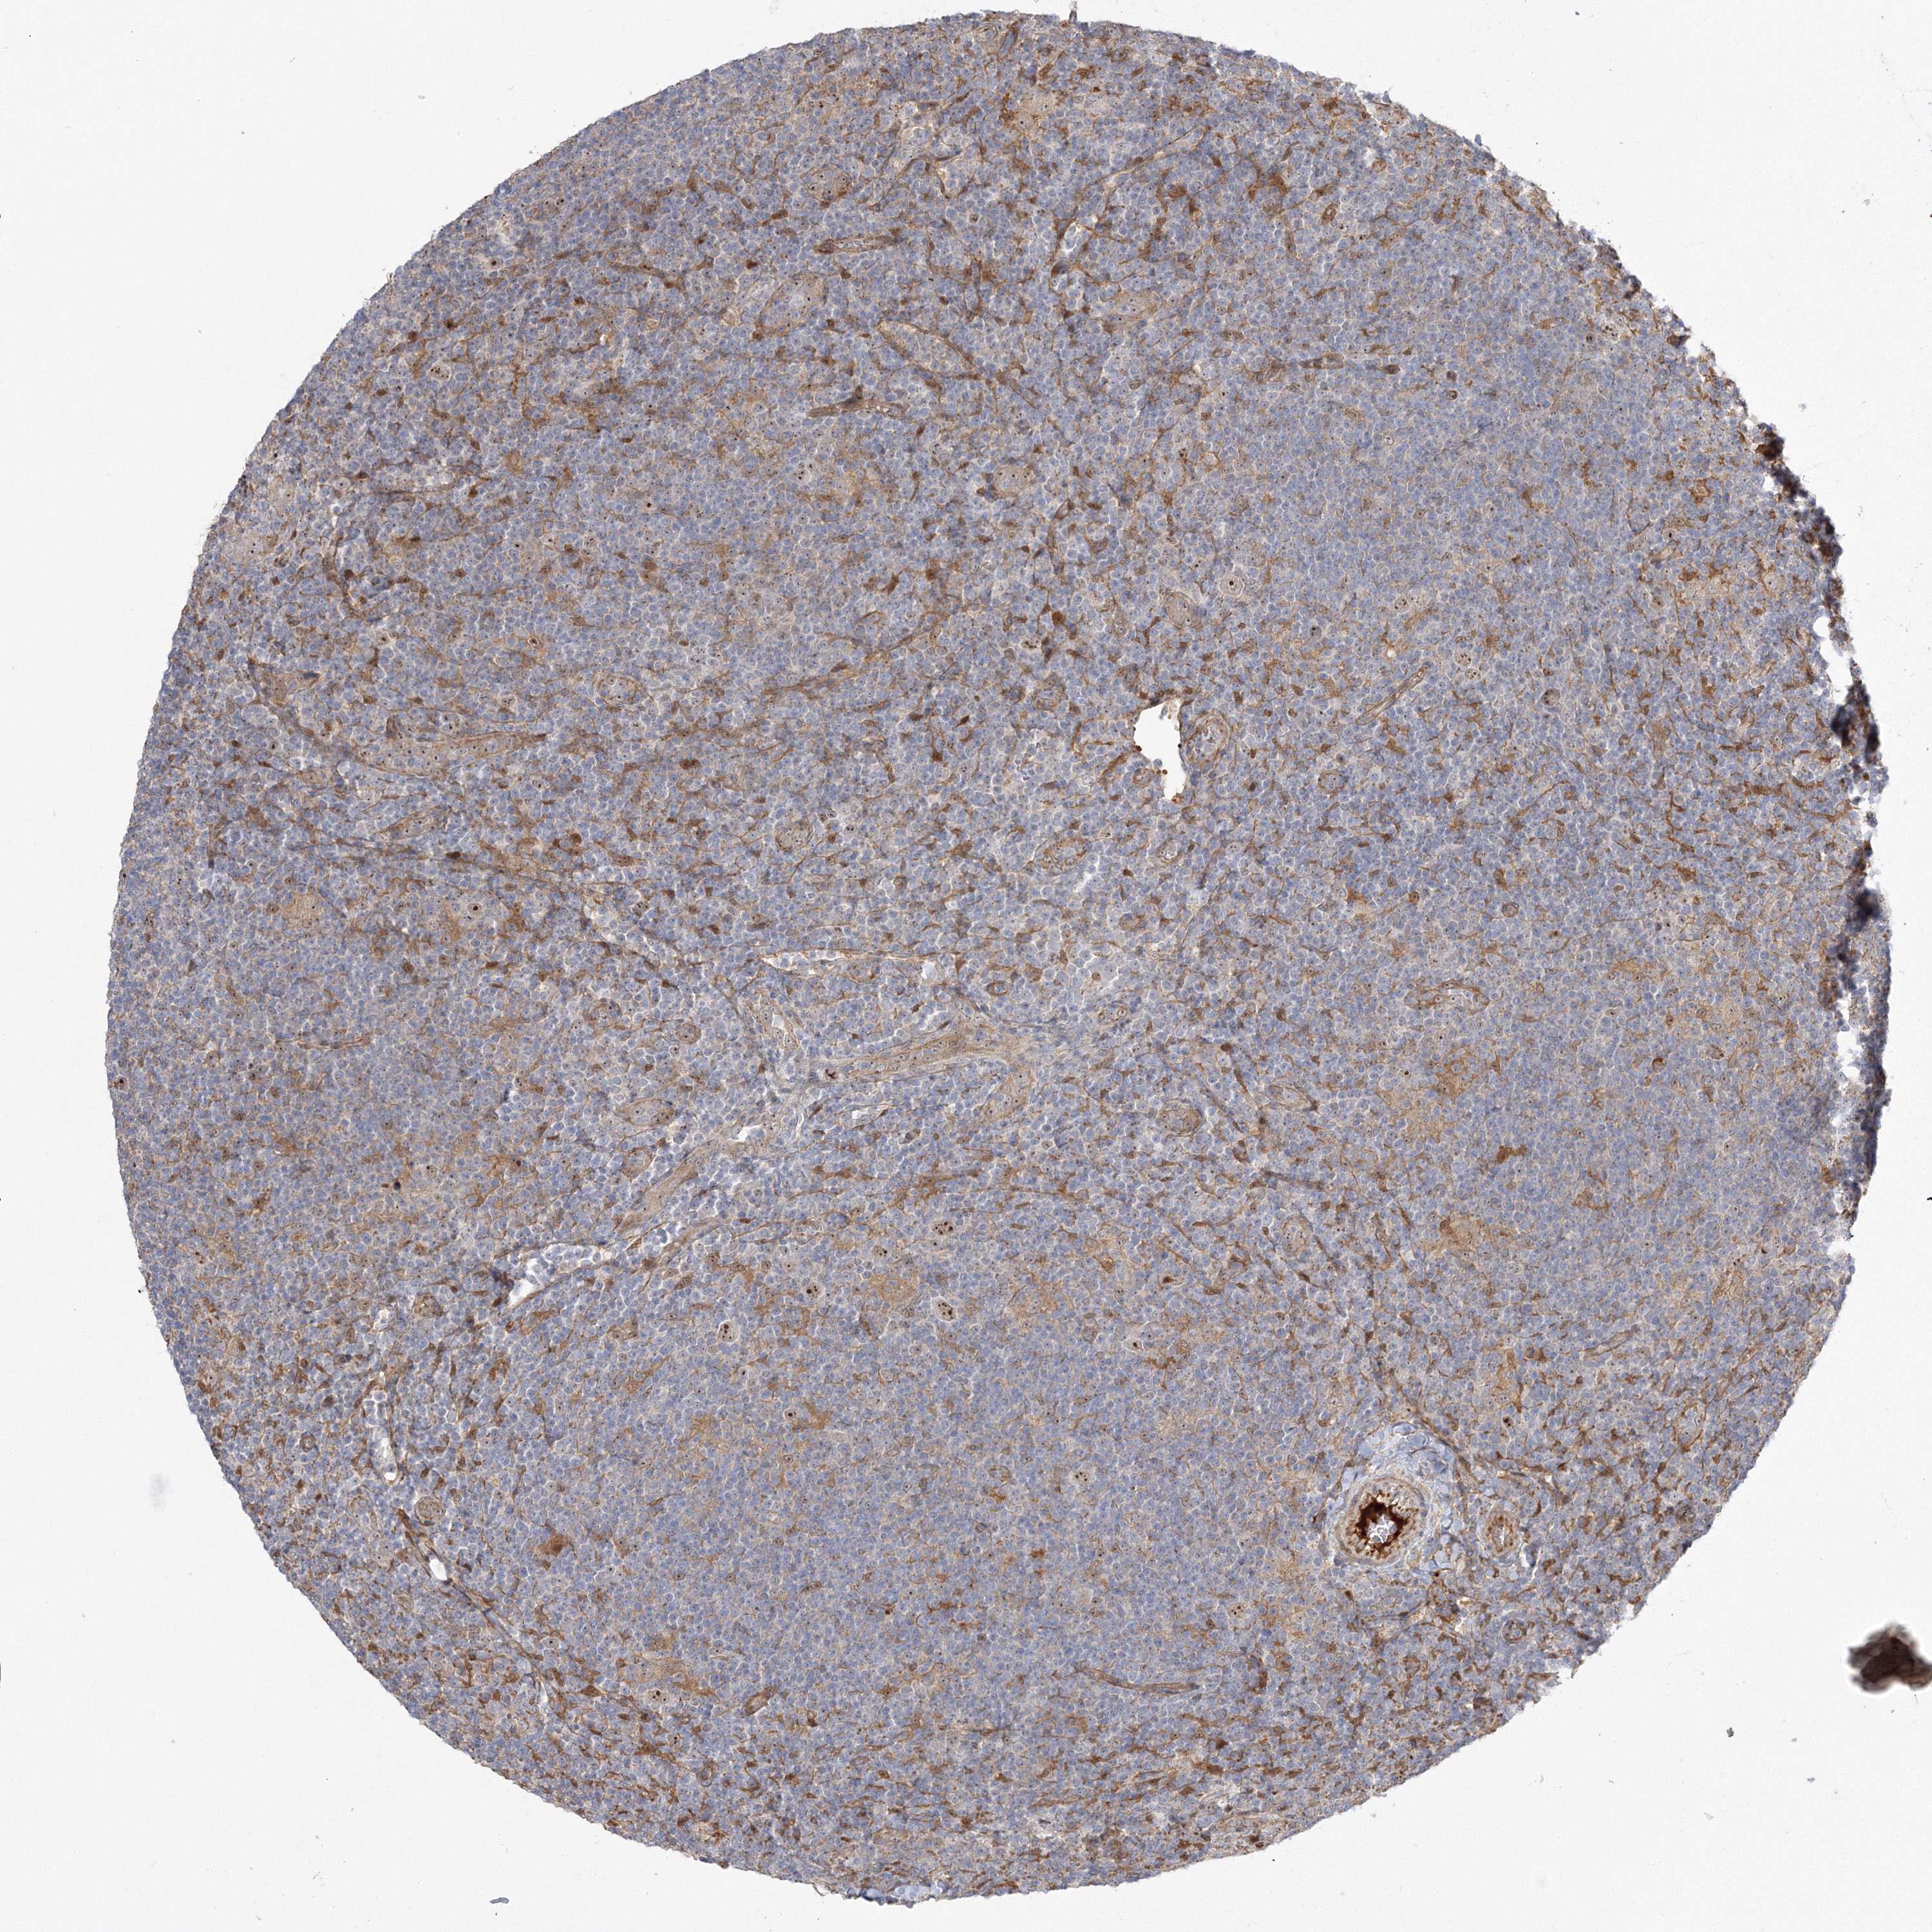

CANCER LYMPHOMA Show tissue menu

LYMPHOMA - Protein expressioni

A mouse-over function shows sample information and annotation data. Click on an image to view it in a full screen mode. Samples can be filtered based on level of antibody staining by selecting one or several of the following categories: high, medium, low and not detected. The assay and annotation is described here.

Antibody stainingi

Antibody staining in the annotated cell types in the current human tissue is reported as not detected, low, medium, or high, based on conventional immunohistochemistry profiling in selected tissues. This score is based on the combination of the staining intensity and fraction of stained cells.

Each image is clickable and will lead to virtual microscopy that enables deeper exploration of all samples and also displays staining intensity scores, fraction scores and subcellular localization as well as patient and tissue information for each sample.

Antibody HPA036295

Antibody HPA036296

Hodgkin's disease, NOS

Malignant lymphoma, non-Hodgkin's type, High grade

Malignant lymphoma, non-Hodgkin's type, Low grade